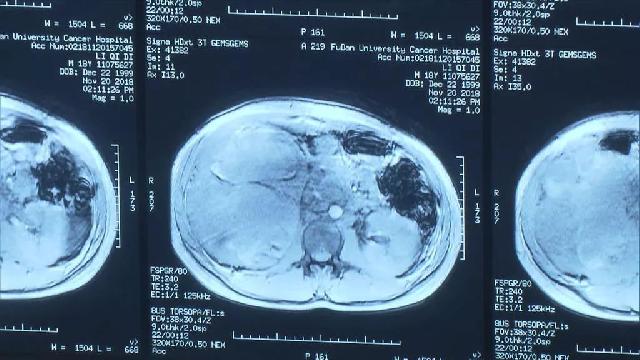

小李被确诊为右肾肿瘤巨大肝转移。

经查,这颗肿瘤长四十厘米,占据肝脏的三分之二!